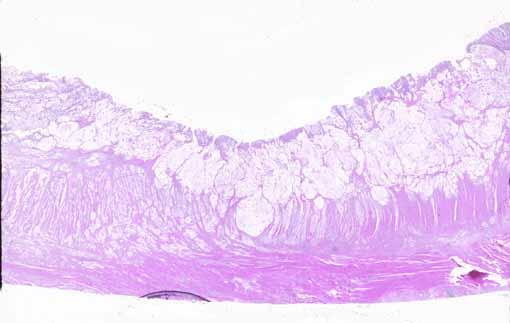

clasificación del pacienteTumor Epitelial Maligno/Carcinoma Mucinoso

parte(separada por órganos)colon/recto

método de exámenMicro

clasificación ectoscópica de tumoresTipo 4(Tipo difusamente infiltrado)/

diámetro mayor del tumor40 -

grado de penetracións(a)